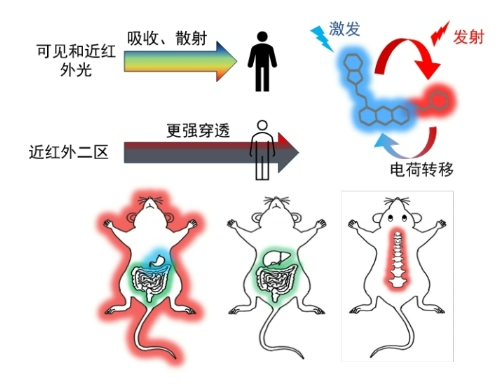

北大新突破:一滴血 查清病从哪来

最近,北京大学何爱彬团队联合多方合作者在国际权威期刊发表最新研究成果。 他们研发出具有自主知识产权的新一代表观液体活检技术cf-EpiTracing,实现仅靠少量血浆样本,就能精准识别病变来源组织、发现早期病2026-03-09 -